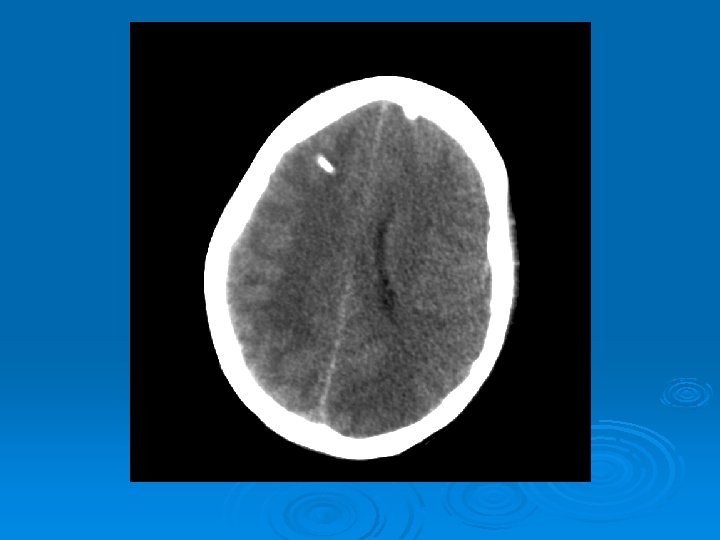

Course: Ø 3 PM, RN noticed anisocoria and L pupil non-reactive. Ø Neurology STAT dose mannitol and w/ dilantin. Ø Pt went for stat head Ct:

CT head 2/11/07 Ø A right frontal ventriculostomy catheter Ø Diffuse sulcal effacement with thickening of the cortex. Ø Loss of gray-white differentiation and hypodensity in the left parietooccipital region. Ø There is diffuse hypodensity of the cerebellum and brainstem. Ø Ø Ø The basilar cisterns are nearly completely effaced. Ø Impression: Ø Worsened diffuse cerebral edema The lateral ventricles are smaller

Course: Ø Neurosurgery saw pt: on exam she had lost cough, gag reflexes, corneal reflexes, she had flexed RUE, semipurposeful with bilateral extended LE. Ø Concern for herniation: placed Ø ICP 35 -40 10 th-11 th EVD